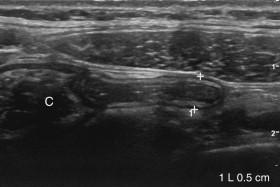

F igure 9-18, Normal appendix. Longitudinal view shows a normal appendix (cursors) measuring 5 mm arising from the cecum (C).